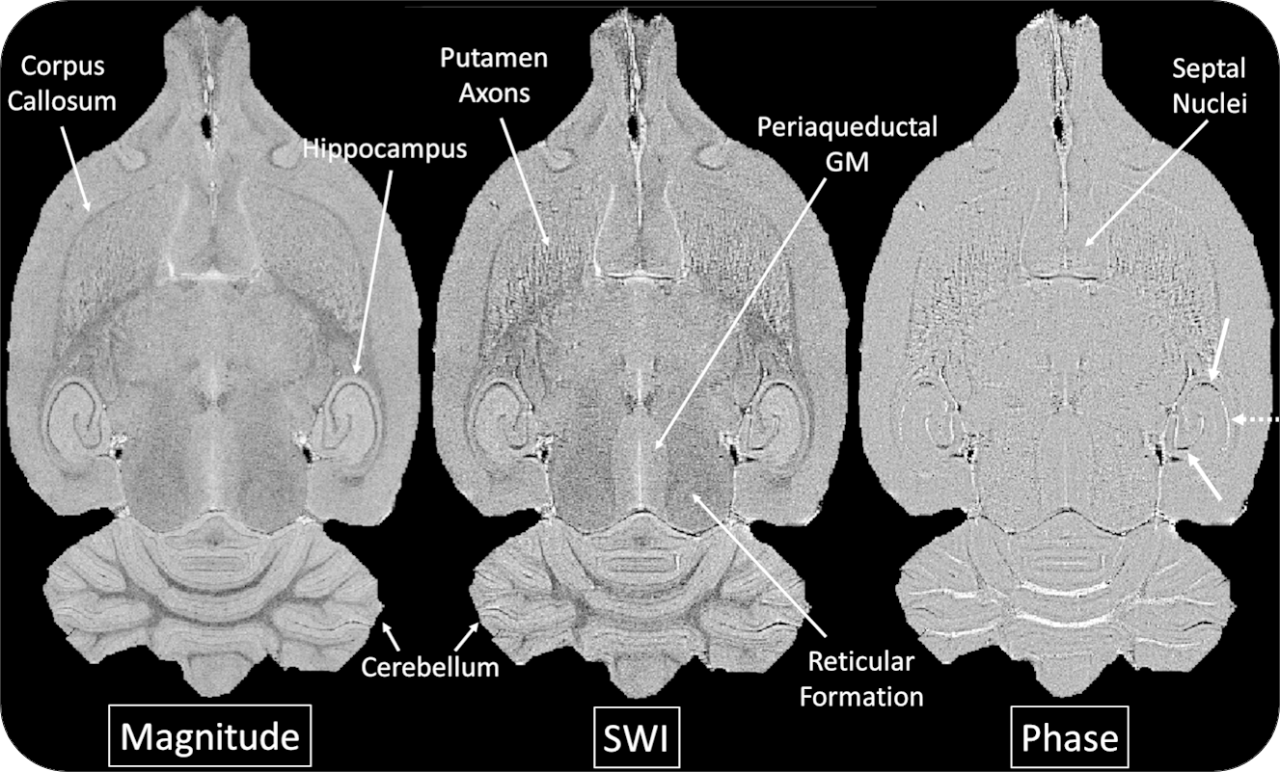

The ultra-high field of the BioSpec 152/11 provides extreme sensitivity for greatest resolution. Its streamlined design for mice studies makes handling simple, while its powerful software guarantees best results. It can be equipped with the MRI CryoProbe to increase sensitivity even further and together with the gradient strength of up to 1000 mT/m, highest resolution is achieved. It is built with nitrogen-free Ultra Shielded and helium Refrigerated (US/R) magnet technology for long service intervals

• Crisp and highly resolved images with native gradient strength of 740 mT/m, upgradable to 1000 mT/m

• MRI CryoProbe for exceptional increase in sensitivity

• MRI sequence portfolio of more than 1,000 sequence variations, including wireless cardiac imaging using navigator based IntraGate methods with cartesian or radial readout, as well as short echo time imaging, such as UTE and ZTE